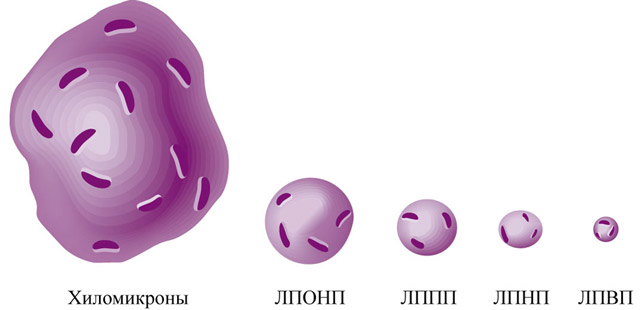

Липопротеины плазмы крови классифицируются по плотности, что определяется методом ультрацентрифугирования. Чем больше липидов в молекуле липопротеина, тем ниже его плотность. Выделяют несколько типов: ЛПОНП, ЛПНП, ЛПВП и хиломикроны. Эта классификация считается наиболее точной и разработана с использованием высокоточного метода ультрацентрифугирования.

Липопротеины также различаются по размерам. Наибольшими являются молекулы хиломикронов, затем идут ЛПОНП, ЛПСП, ЛПНП и ЛПВП, уменьшаясь по размеру.